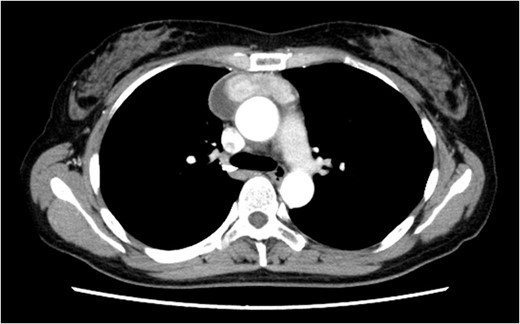

On post-operative day 17, she visited our hospital for a routine follow-up, and her chest X-ray revealed a massive right pleural effusion (Fig. 3). Therefore, she was re-admitted to our hospital and right chest drainage was performed. Milky and turbid fluid was drained with an amount of ~3100 ml. The biochemical analysis of pleural fluid revealed a triglyceride level of 1420 mg/dl, and we confirmed a diagnosis of chylothorax. She received fasting and total parenteral nutrition. The fluid via chest tubes returned to be clear with its amount of <200 ml for a day.

Chest X-ray on post-operative day 17 revealing massive pleural effusion.